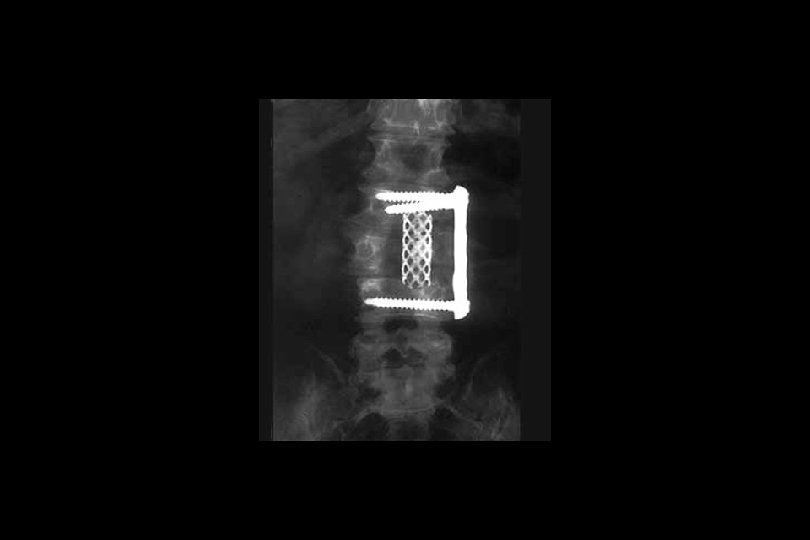

Omurga yaralanmaları • Faset eklem kilitlenmeleri: Genellikle tek yanlı kilitlenmelerde %25’lik, iki yanlı kilitlenmelerde ise %50’den fazla yer değiştirme söz konusudur. AP grafide spinoz çıkıntılar aynı hatta değildir. • T 1 -T 10 kırıkları: Mekanizma genellikle hiperfleksiyondur. Göğüs kafesi nedeniyle bu bölgedeki çökme kırıkları genellikle stabildir. Kifoz 30°den fazla ise ameliyat gereklidir.

Omurga yaralanmaları • T 11 -L 1 kırıkları: Mekanizma çoğu kez ani hiperfleksiyon ve rotasyon kombinasyonu şeklindedir. Çoğu kez anstabildir. • Lomber kırıklar: Çoğu kez ani hiperfleksiyon sonucu oluşurlar.